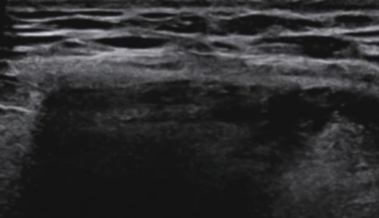

Paroi normale

Hernie